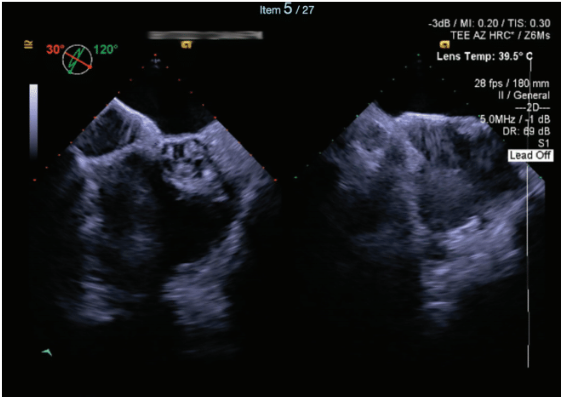

Due to the complexity of the transseptal puncture, the decision was made to have 2 operators perform the case. To ensure the most accurate visualization of the ASD occluder and the target puncture site, 4-dimensional TEE was utilized as a guide.

Two transseptal punctures were attempted, but due to the large, nearly occlusive ASD device, only a single transseptal access was secured. A 98-cm Brokenbrough needle and electrocautery was utilized to localize the posterior superior lip of the available fossa. After transseptal access, the sheath was then advanced over a 0.35” J-wire into the LA. Using the Agilis sheath, a PentaRay diagnostic catheter (Johnson & Johnson MedTech) was advanced into the LA and the entire LA was mapped. The SL-1 sheath was kept in the right atrium (RA) with irrigation.

TEE can be a superior tool in guiding transseptal puncture, particularly in complex AF cases, where anatomical challenges such as a prior ASD or patent foramen ovale (PFO) closure device are present. TEE provides real-time, high-resolution imaging that enhances the precision of catheter placement during transseptal puncture, reducing the risk of complications associated with inadvertent puncture of adjacent structures. In patients with prior large ASD or PFO devices, where the anatomy of the interatrial septum may be significantly altered, the ability of TEE to clearly delineate the septum and device margins is invaluable, ensuring that the puncture is performed safely and accurately. This utility makes intraprocedural TEE an essential modality in the management of such high-risk cases, optimizing outcomes and minimizing procedural risks. Although we frequently utilize ICE during AF ablations, our operators prefer the utility of TEE when encountering challenging transseptal punctures such as this case. The limitations of obtaining consistent access to intraprocedural TEE given the scarcity of cardiac anesthesia coverage is an unfortunate reality; however, we specifically request such assistance and plan for this coverage when facing complex transseptal puncture cases.